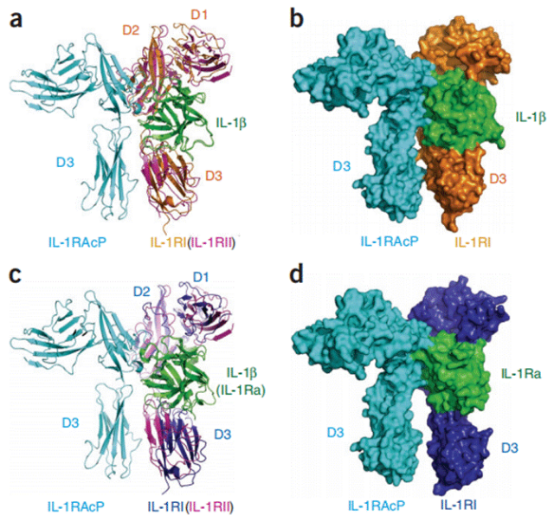

IL-1β的信号转导主要通过IL-1β受体相关激酶途径(IPAK途径)介导。首先IL-1β与IL-1R结合后,IL-1β,IL-1R I型(IL-1R1)和IL-1R辅助蛋白(IL-1Racp)形成异源三聚体;蛋白激酶4(IPAK4)和骨髓分化因子-88(MyD88)被活化,同时IL-1R活化蛋白激酶4自身磷酸化,IPAK1和IPAK2磷酸化,接着招募寡聚化肿瘤坏死因子受体相关因子(TRAF6),活化的TRAF6使有丝分裂原结合蛋白激酶MAPKKK家族活化;然后核内转录因子诱导激酶(NIK)被激活,被解除抑制的核转录因子(NF-κB)转入细胞核,调节相关基因的表达。

图1. IL-1β信号转导

图3. 基于结合配体的IL-1β-IL-1RI和IL-1Ra-IL-1RI在IL-1β-IL-1RII-IL-1RAcP上的叠加

nature immunology DOI:(10.1038/ni.1925)